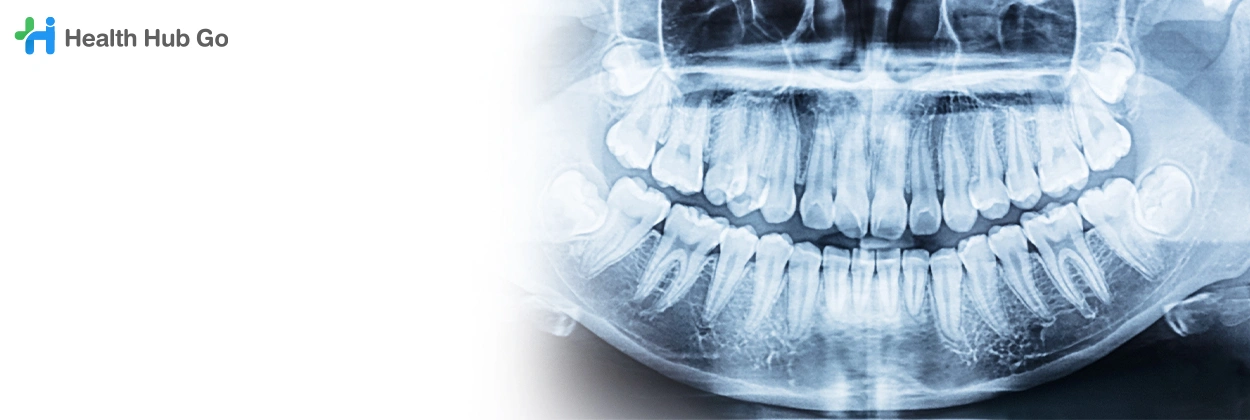

เอกซเรย์ฟัน

Dental X-ray